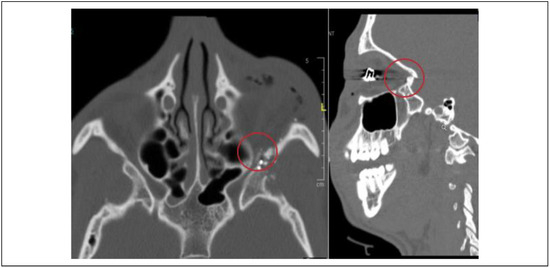

In addition to muscle entrapment, many other types of periorbital and globe injuries were diagnosed in our pediatric cohort. Complex eyelid lacerations were requiring operative intervention occurred in seven patients, with two of these patients requiring canthal repositioning. There were five cases of lacrimal/canalicular injury, five cases of traumatic optic neuropathy, and three cases of hyphema. Two patients had ruptured globe requiring enucleation. One patient had direct injury to the optic nerve by gunshot wound to the orbit penetrating the optic canal (Figure 3).

Figure 3.

Direct injury to the optic canal and optic nerve by gunshot wound.